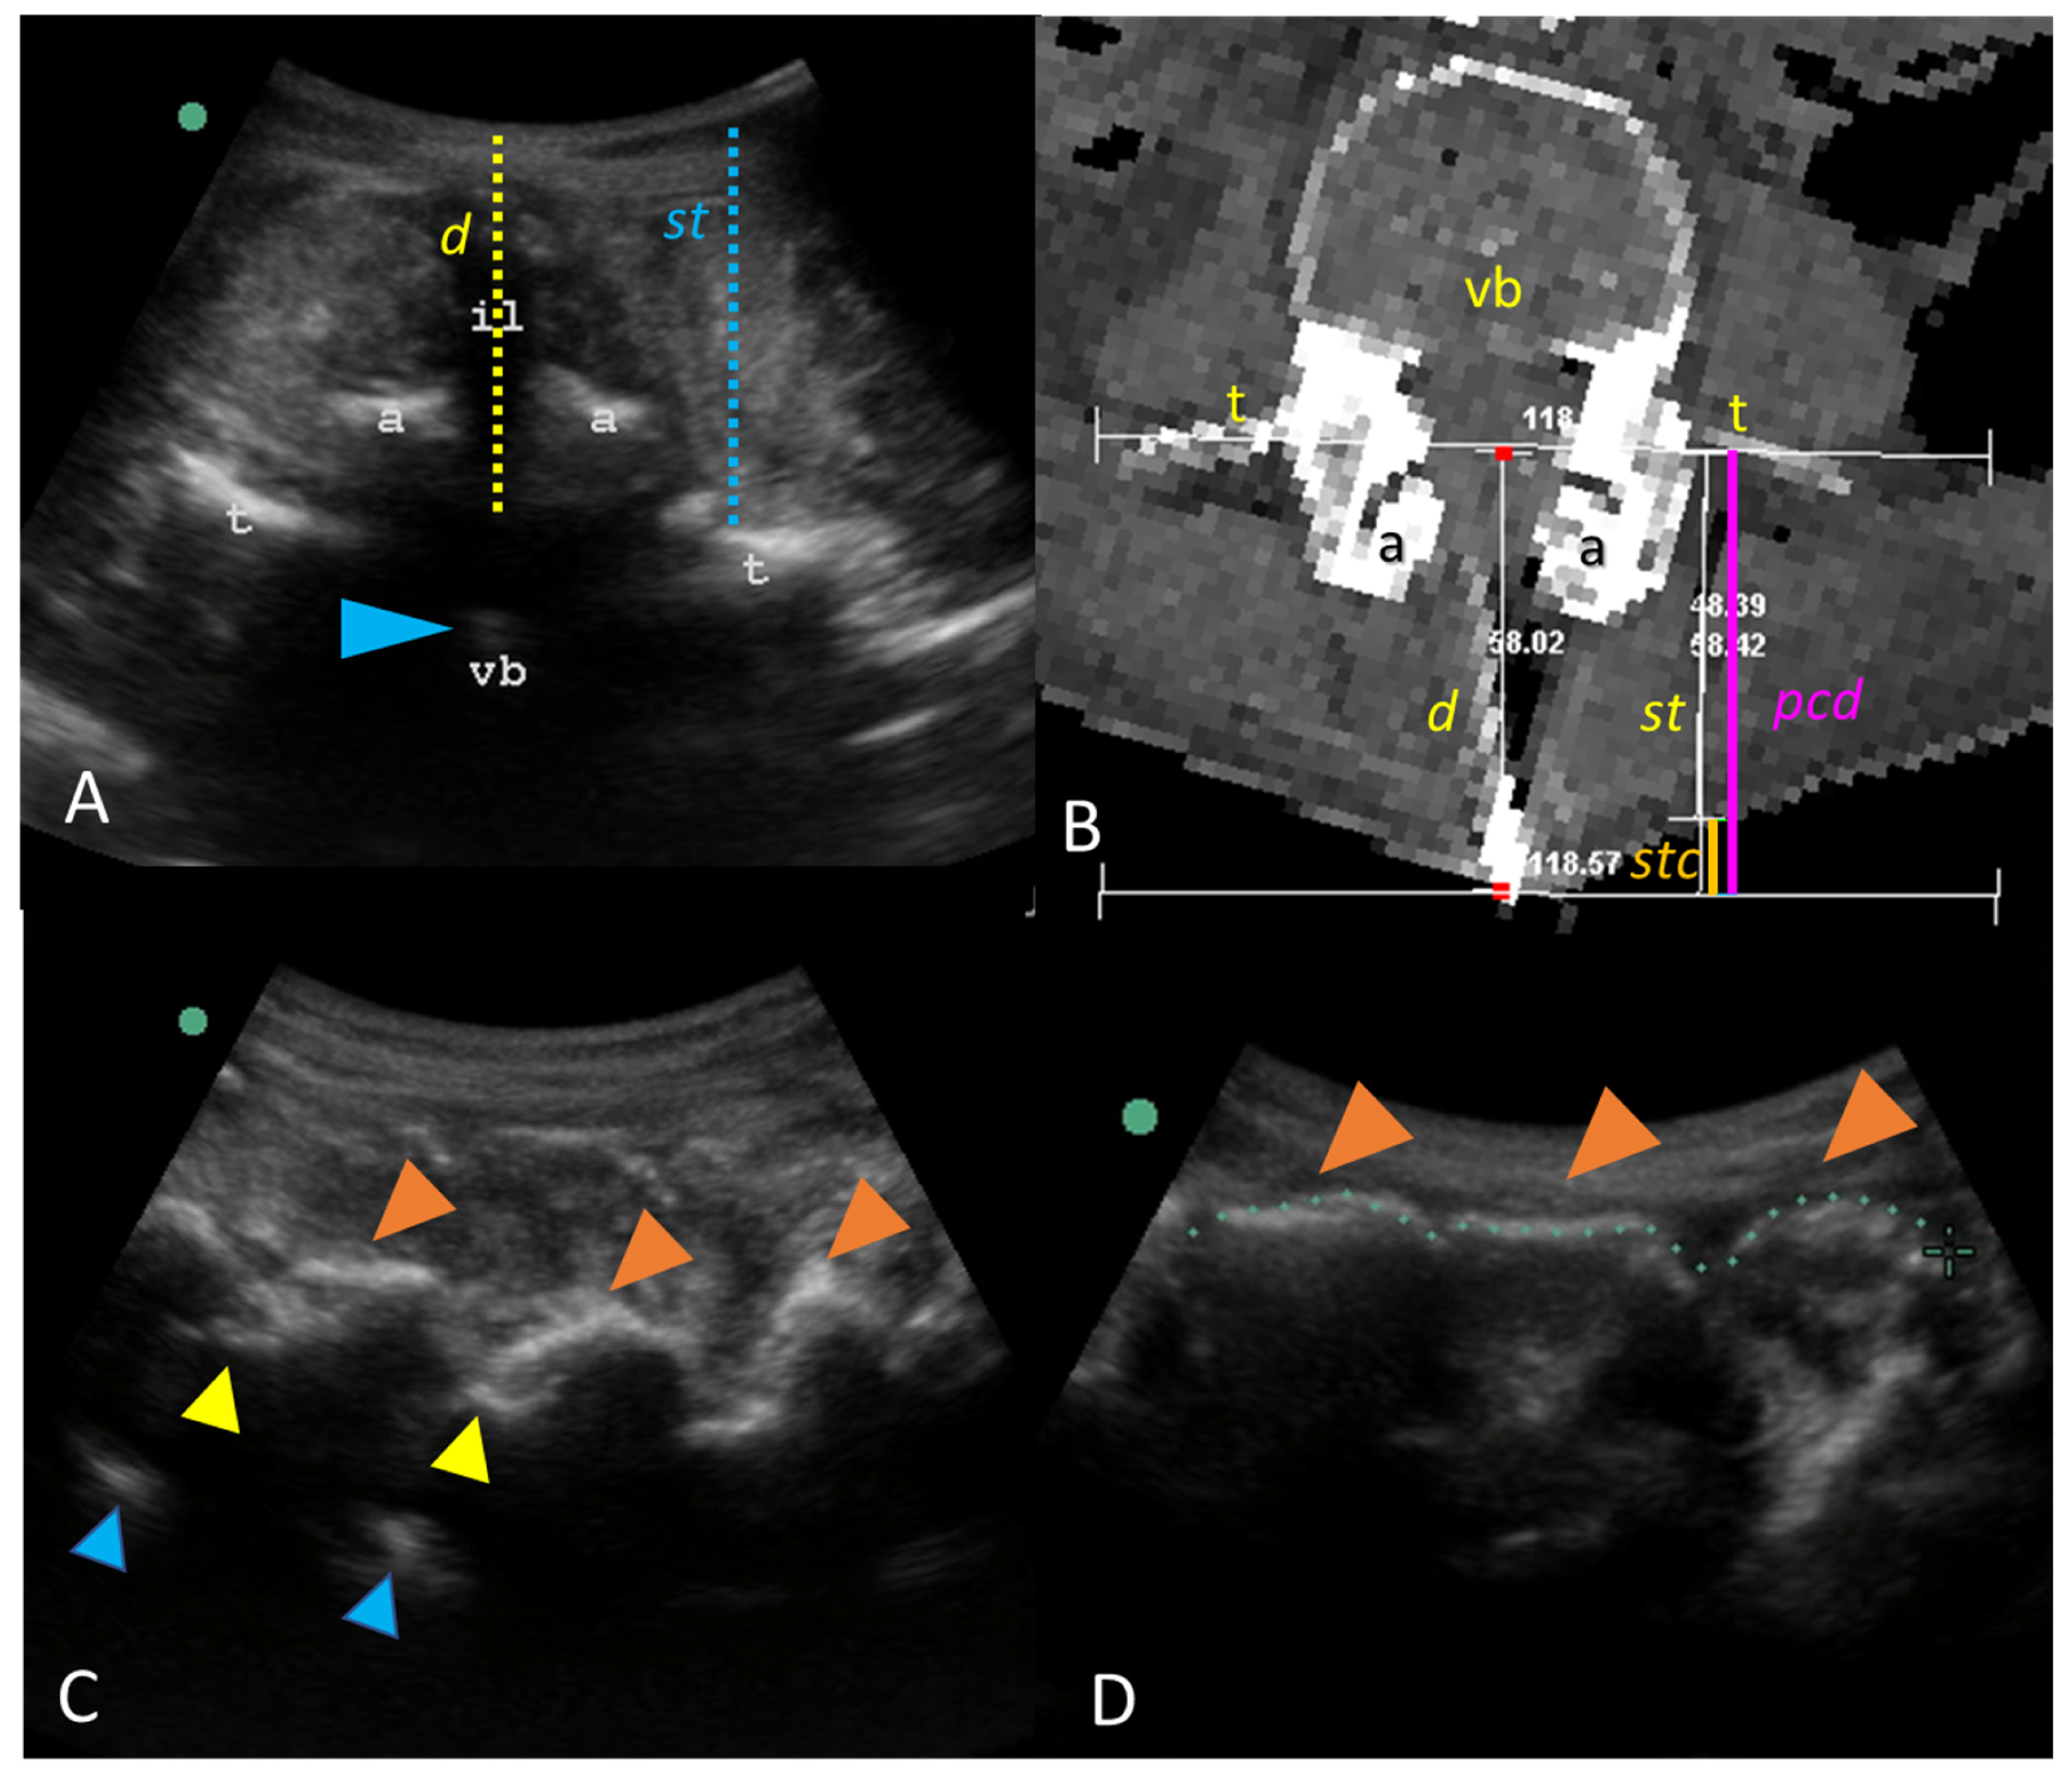

2.3. Visual Guidance of Needle Insertion

2.4. Needle Insertion

2.5. CT and 3D Reconstruction